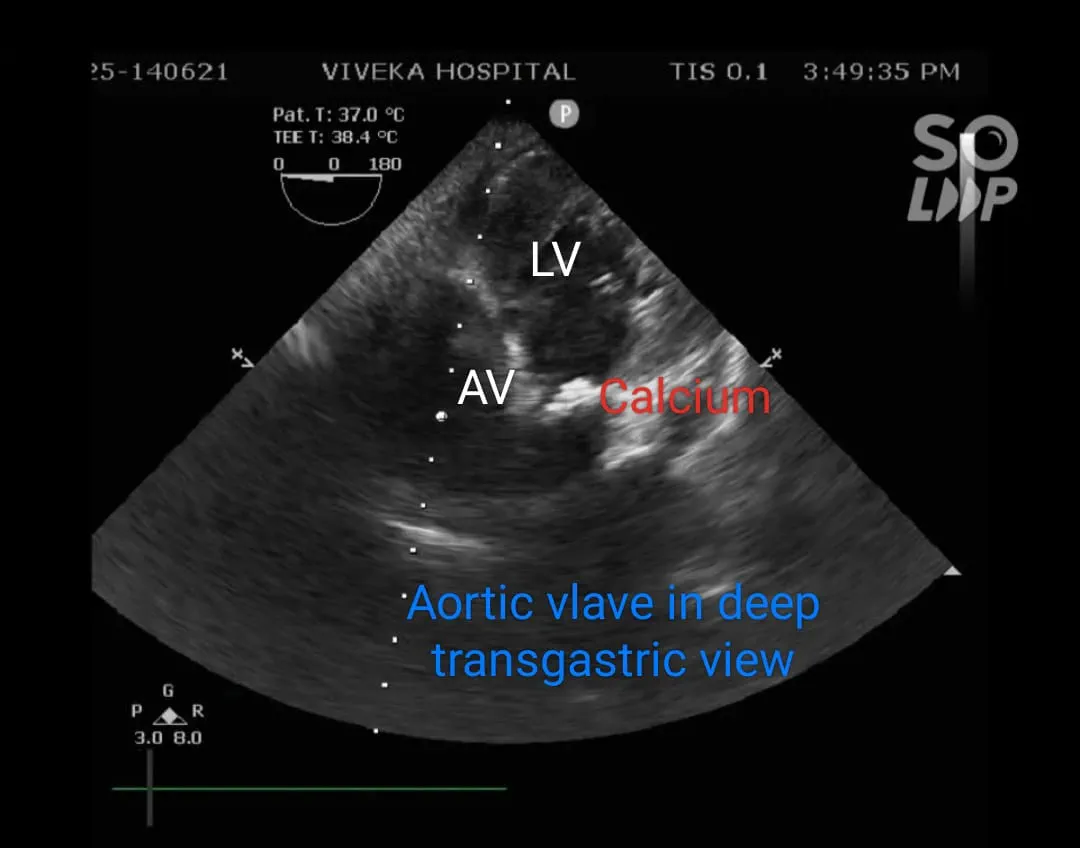

Transoesophageal echocardiography: Findings of Transthoracic ECHO confirmed. Aortic annulus : 20.1mm

Gradient : 128/50 mm of Hg. Mild Aortic regurgitation. Severe Concentric Left ventricular hypertrophy. Calcific Aortic Valve with area 0.349 cm2.

Findings after opening aorta: Aortic Valve was bicuspid and heavily calcified. Indigenous aortic valve excised and calcium debrided.

- Our patient didn’t have any of the risk factors. RV ischaemia due to embolism of calcific material in the RV branch is probably the cause of RV dysfunction in our patient and this was treated with the grafting.